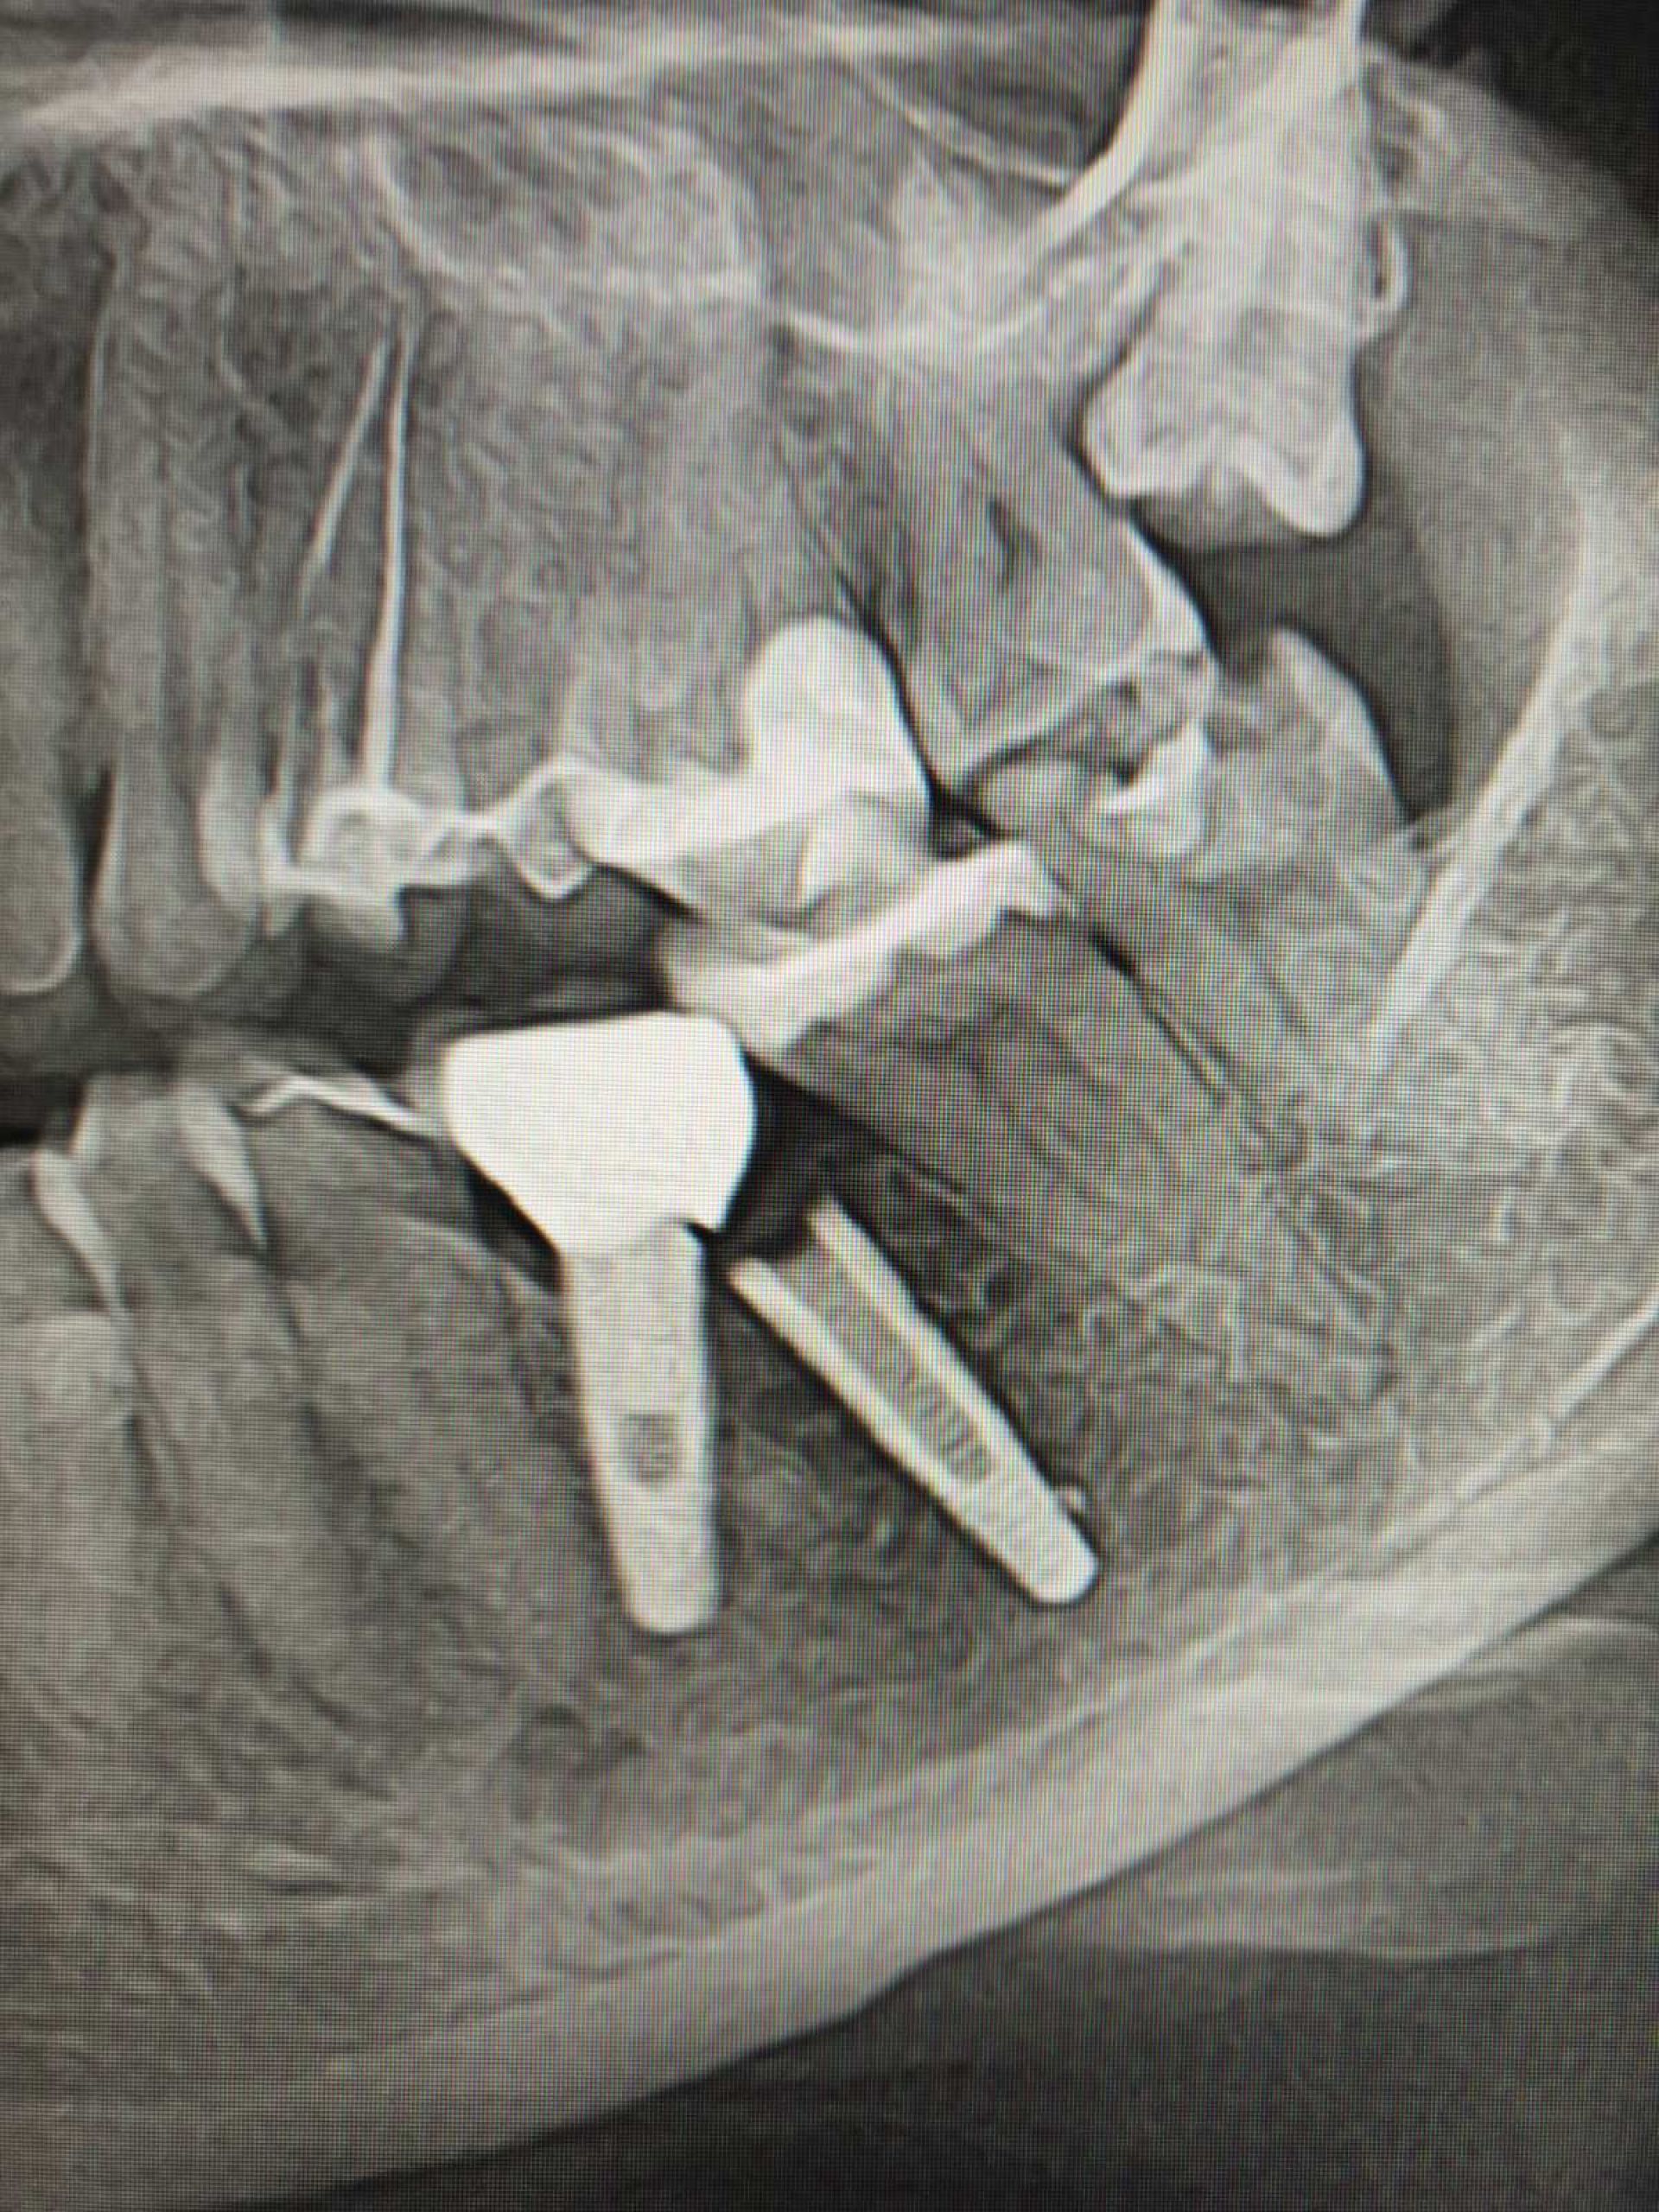

Ще один важливий фактор, який вигідно відрізняє клініку INNOVA від конкурентів – власний комп'ютерний томограф. Таким чином, можливо провести комплексну діагностику перед плануванням операції. Дані КТ зубів дозволяють не лише оцінити стан кістки пацієнта, а також дозволяють виготовити спеціальні хірургічні шаблони для майбутньої операції та оцінити становище імплантату відразу після операції.

Техніка одномоментної імплантації: сучасна методика, під час якої встановлення імпланту проходить одразу після видалення зуба. Фактично, дві складні процедури (видалення зуба і встановлення імпланту) виконується за один візит, Але у випадках, коли пацієнт потребує відновлення давно втрачених зубів, лікар розглядатиме інші техніки.

В МНВЦ "Плоскирів" найголовнішим критерієм є якіст послуг і для цього у них є все: досвідчені лікарі, кращі матеріали, найсучасніші цифрові 3D-технології, обладнання та власна зубопротезна лабораторія.